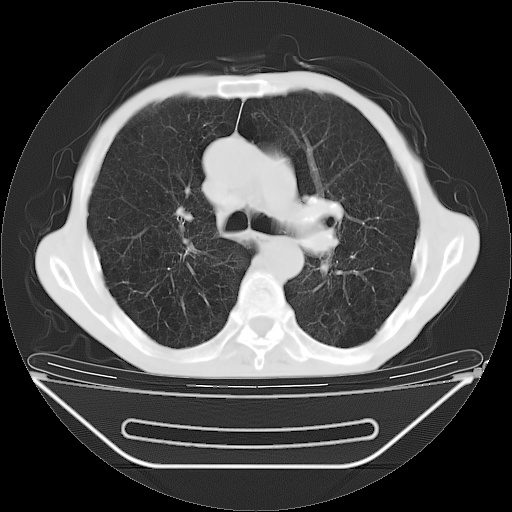

以下是引用zsl6918在2008-8-25 21:55:00的发言:[br]符合右肺周围性肺癌并肺内转移,左肺结核球。双肺肺气肿。腰椎附件转移。

以下是引用随光逐影在2008-8-25 22:03:00的发言:[br]1)考虑右肺下叶周围性肺癌并肺内转移,腰椎附件转移。2)左上肺结核(结核球形成)。3)双肺肺气肿(多发肺大泡形成)。4)双肺门区及纵隔内多发淋巴结钙化。